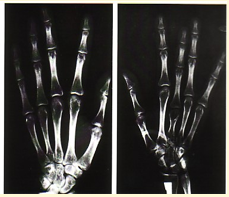

What is DACTYLITIS?

Fingertips lost due to infarction